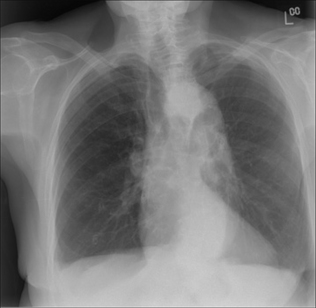

image

Figure 23.2 Westermark sign? Be careful. Elderly female. Dyspnoeic. A PE is a clinical possibility. The right lung is hypertransradiant (blacker than the left lung). We need to be cautious and not too quick to call this the Westermark sign of PE. Two technical factors are causing the blackening on this CXR: (1) rotation to the right; (2) lateral decentering of the x-ray beam to the right side…this is evident from the increased definition of the scapula and soft tissues on the right side as compared to the left side.